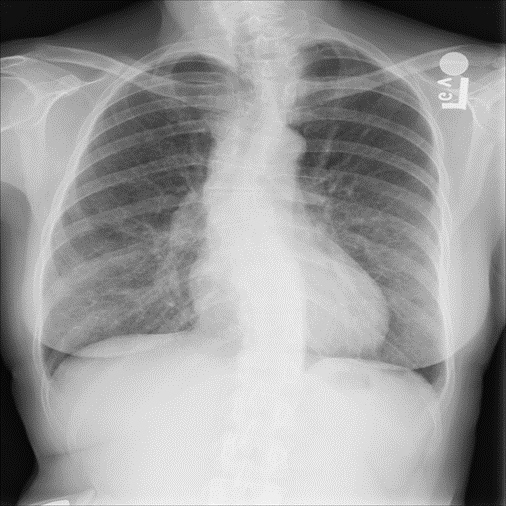

Refer to caption

Figure 15: Fictional image of a BCT generated with the flow-based generative model.

Finally, a fictional image generated for BCTs is shown in Fig. 15.